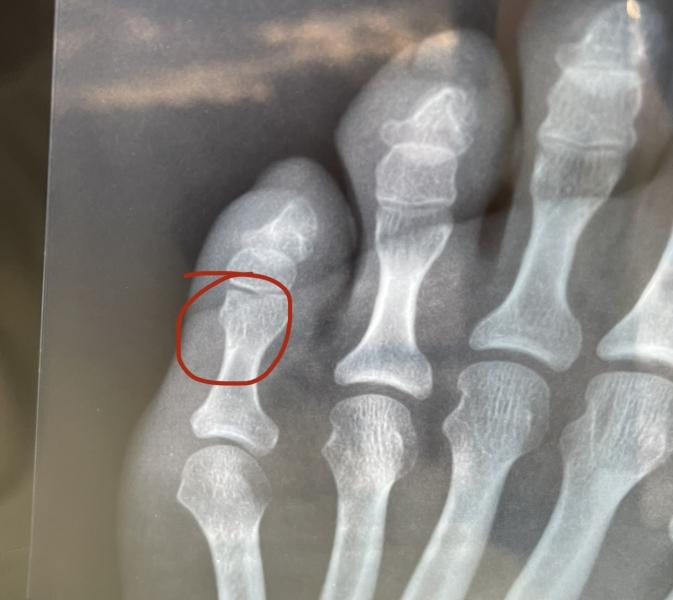

4 января в травме сделали рентген и сказали,что перелом.

Сегодня поехала в свою поликлинику,там сделали рентген и сказали,что перелома нет 😑

Я сходила в травмпункт и попросила распечатать рентген ибо в моей поликлинике от работы не дают на руки снимки. И загвоздка в том,что при переломах нам работа выплачивает страховку. Вот я и думаю кто прав🤔

В моей поликлинике сказали,что ушиб и дали больничный до 12 января,вот хочу приехать и показать этот снимок. ...